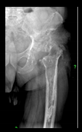

The radiological examination allowed us to verify the close bone-to-implant contact and the unchanged position of the implant during follow-up.

In all the cases operated with the above-described targeting procedure, the stems of the cups remained between the cortical bone surfaces without perforation of the linea terminalis, as shown by postoperative radiographs. There were no complicated surgical situations. In 16 cases, the wound healings were uneventful, and the hips were able to bear weight again after postoperative rehabilitation.

The only patient who suffered an infection healed after the removal of the implant. This complication rate is known and in line with accepted values.